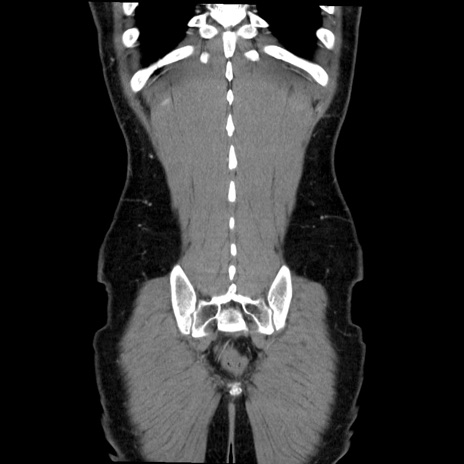

症例36(冠状断像)

【症例】20歳代 男性

【主訴】心窩部痛

【現病歴】今朝より上腹部痛あり。一旦軽快していたが再度出現したため救急要請。昨日夕に白身の魚を含む刺身を食べた。

【身体所見】BP 136/89mmHg、HR 74/min、BT 37.0℃、腹部:膨満、軟、心窩部に圧痛あり。反跳痛なし、筋性防御なし、腸雑音やや亢進あり。

【データ】WBC 17700、CRP 0.48